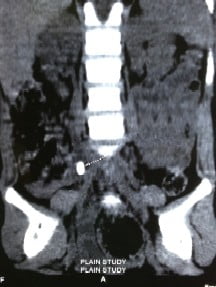

ureteric calculi

When children experience the above symptoms, urine is tested in the lab. Presence of excess red cells or white cells; and presence of crystals in the urine suggests urinary stone disease. Ultrasound scan helps to find out whether there is a stone, the position, size and number of stones. In addition special tests like IVP, X-Ray, or CT scan may be required.